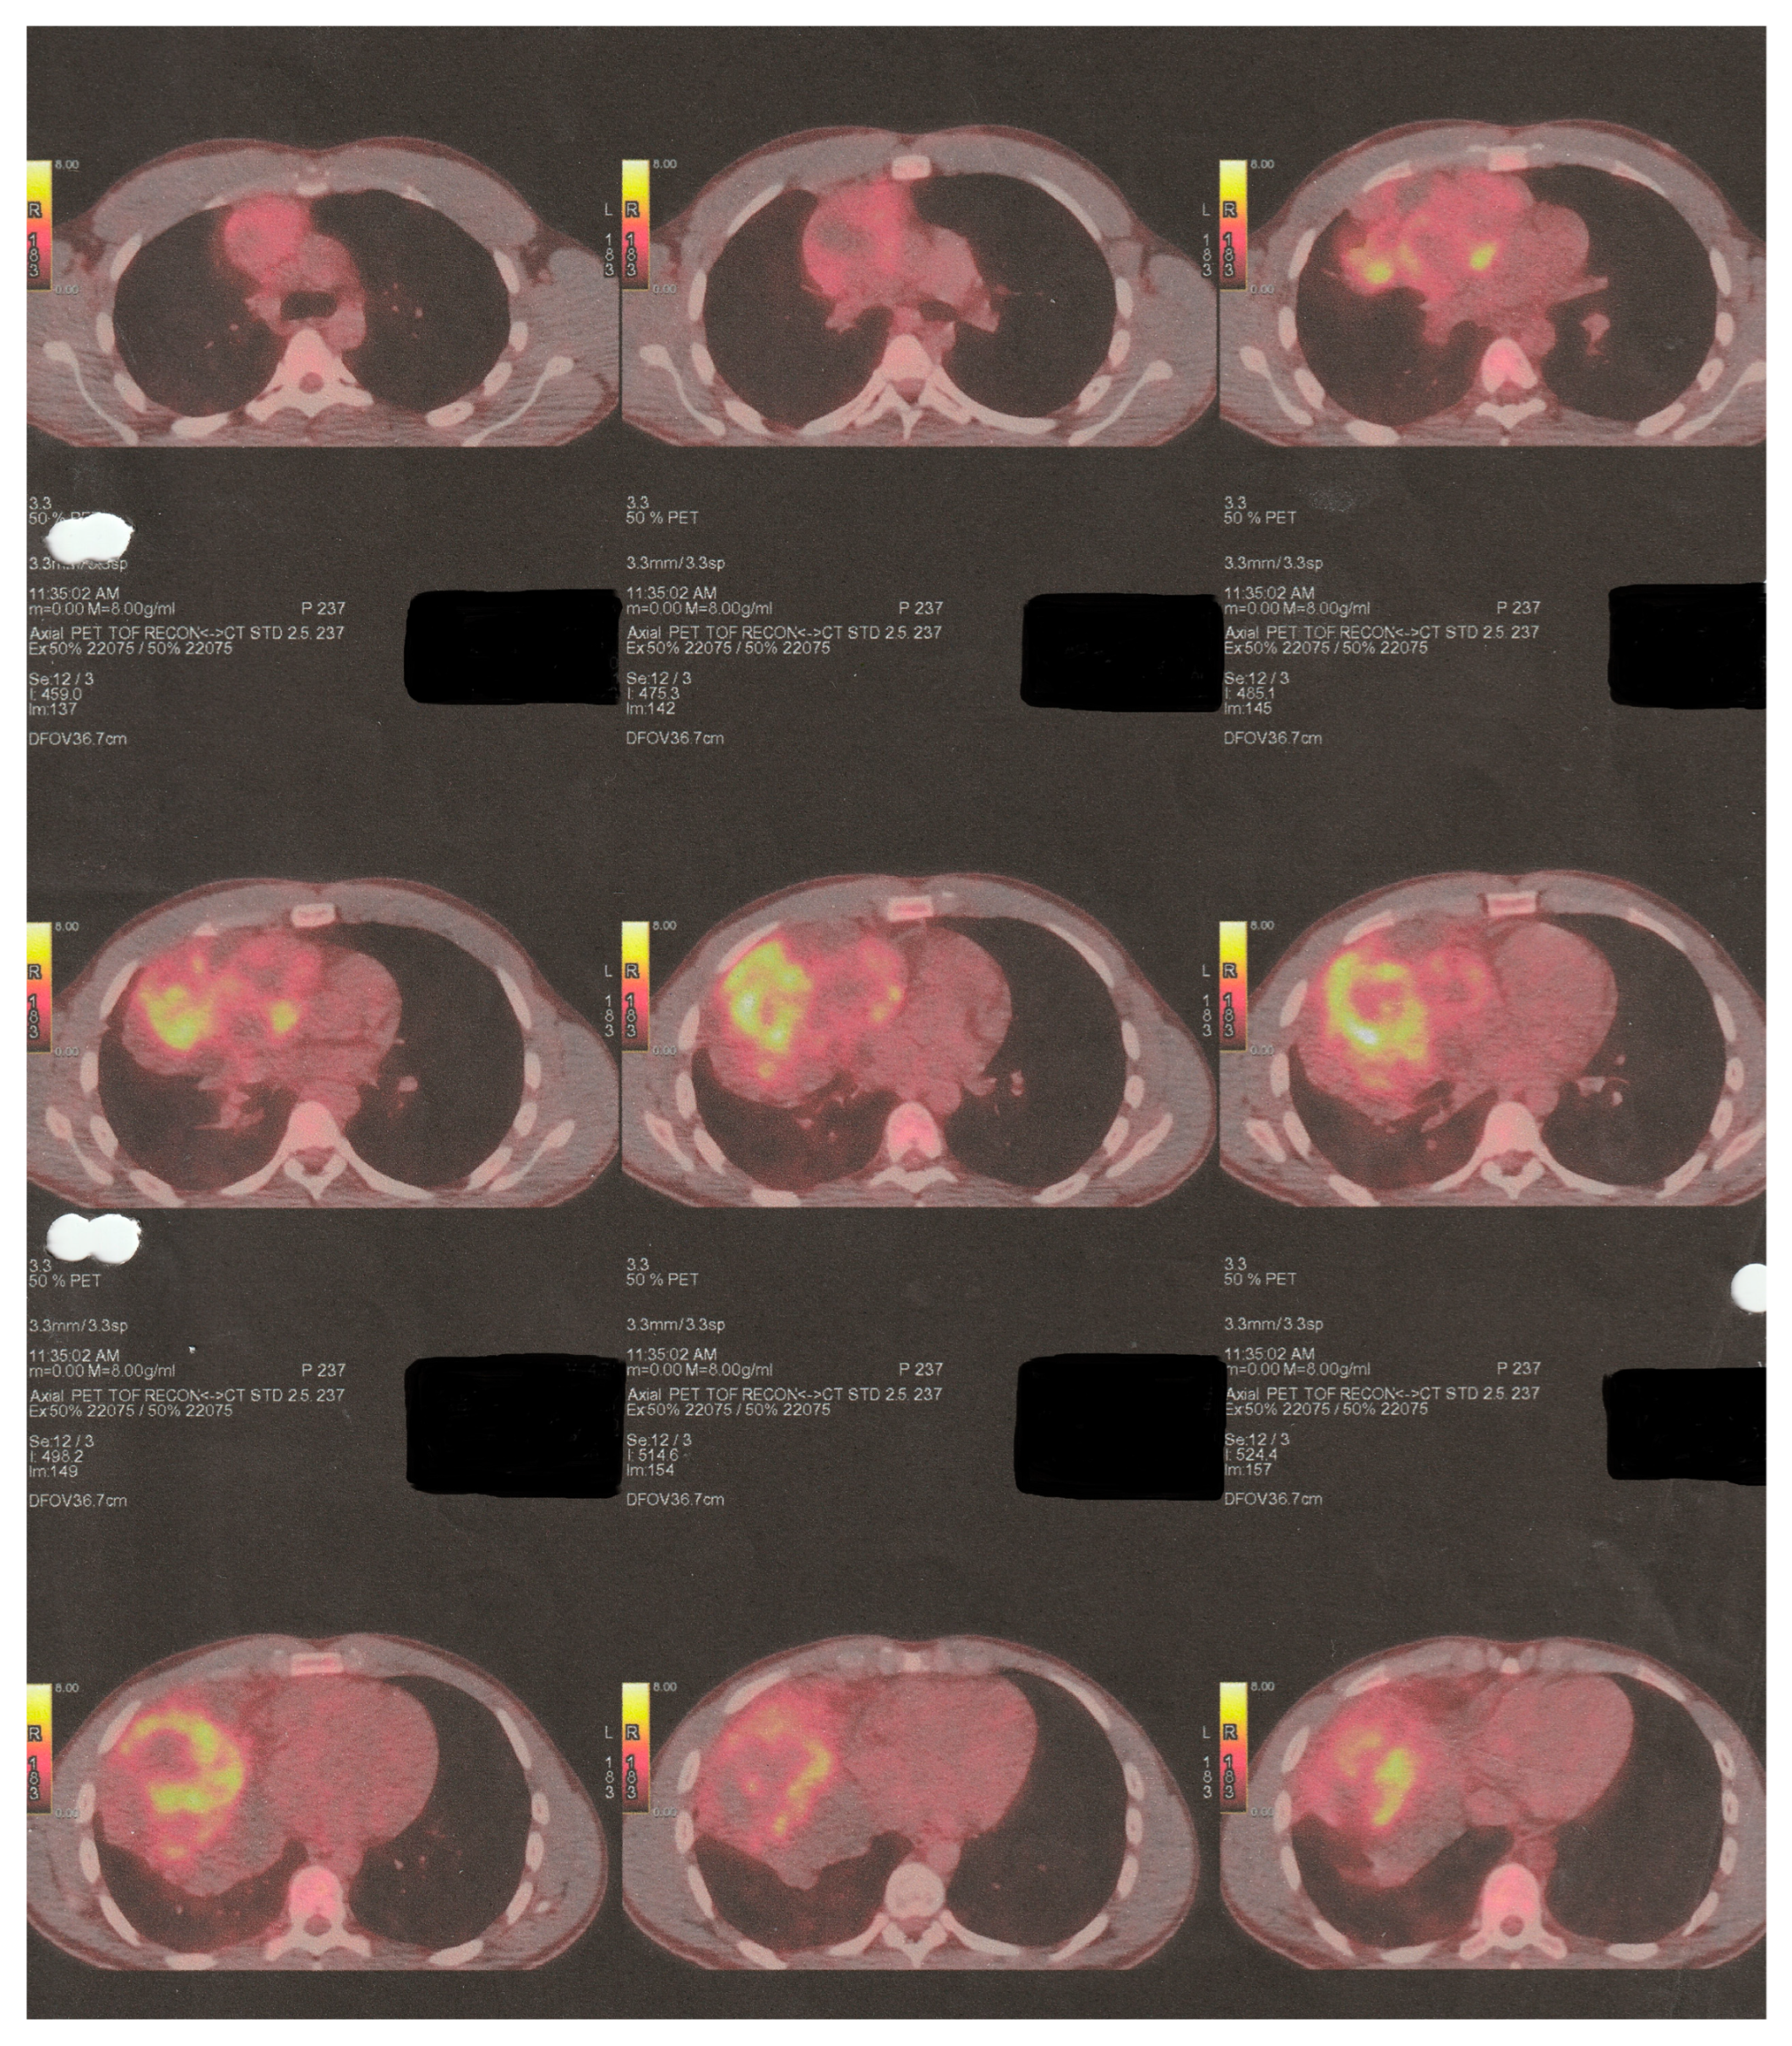

The following imaging procedures that took place, such as high-resolution chest computer tomography (chest CT) and positron emission tomography–computed tomography (PET-CT), confirmed the presence of an heterogenous anterior and middle mediastinal voluminous formation, extending into the (R) lung cavity, with quite notable size measurements (DMax: ~11 cm × 10 cm × 13 cm), a significant standardized uptake value (SUV: 8.7), areas of cystic degeneration, necrosis, and associated pleural effusion (Figure 1).

The tumor applied additional pressure on both (R) heart chambers, causing tracheobronchial compression and mediastinal shift. The PET-CT imaging process identified hypermetabolic foci in mediastinal lymph nodes and neighboring osseous structures, suggesting additional metastatic spread.

Figure 1. Initial preoperative PET-CT imaging control.